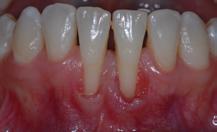

Figure 7.2 : Récessions gingivales sur les 2 incisives centrales mandibulaires. L’absence de gencive attachée sur les faces vestibulaires rend le brossage pénible et délicat. La gencive est inflammatoire. Une greffe est nécessaire pour recréer un bandeau de gencive kératinisée.

7.1 QU’EST-CE QU’UNE RÉCESSION GINGIVALE ?

Une récession gingivale, encore appelée dénudation radiculaire ou déhiscence est une dénudation partielle de la face extérieure des racines, nommée face vestibulaire (face visible) due à la migration de la gencive. Elle n’est pas d’origine bactérienne mais plutôt traumatique. De fait, elle n’est pas un signe de parodontite.

Une gencive anatomiquement fine, soit naturellement, soit du fait d’une position excentrée de la dent sur l’arcade, associée à un brossage traumatique ou encore à des mouvements orthodontiques qui déplacent la dent vers

l’extérieur pour permettre son alignement sont autant de causes d’apparition d’une récession gingivale.

En aucun cas, la récession gingivale ne peut être responsable à elle seule de la perte de la dent.

En revanche, elle peut rapidement rendre la dent hypersensible aux variations thermiques ou à certains aliments. Elle complique le brossage car la limite dent-gencive ne se trouve

plus au même niveau que la dent adjacente. Une inflammation gingivale peut s’installer, rendant la zone sensible. Enfin elle peut être jugée inesthétique en donnant l’impression visuelle d’une dent très longue.